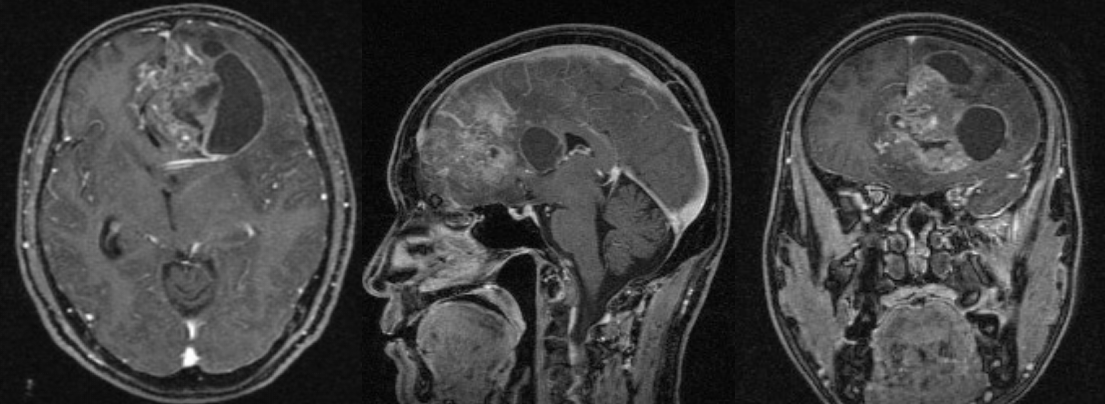

术后半年MRI增强